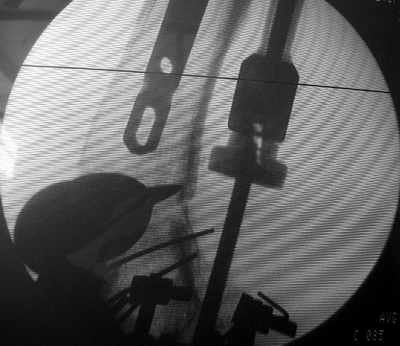

В итоге сделали антеградный остеосинтез. В дистракторе свежий перелом вправился сразу, а вот старый - оставил проблему, дистальный отлмомк остался все равно кзади. И гвоздь бы прошел кпереди от него, а ретроградный - перфорировал бы передний кортекс. Так что пришлось еще сделать чрескожную остеотомию через перелом, чтобы малость мобилизовать дистальный отломок. Снимки в прилжении.

The osteotomy was perfromed trough the fracture site. See the image.